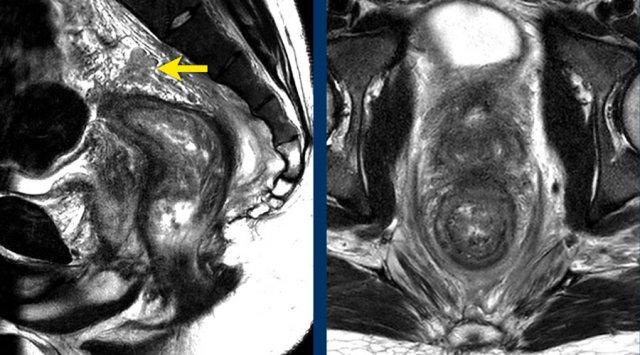

Hình ảnh

Đâykhối u hình vành khuyên một phần (8–12 giờ)Xâm lấn mỡ quanh trực tràng, với bờ MRF phía trước <1 mm (mũi tên), phù hợp với cT3ab MRF+.

- Lớp cơ niêm mạc nguyên vẹn có thể nhìn thấy từ vị trí 12 giờ đến 8 giờ

- Gián đoạn lớp cơ phía bên phải, với khối u dạng nốt xâm lấn vào mỡ quanh trực tràng (đầu mũi tên)